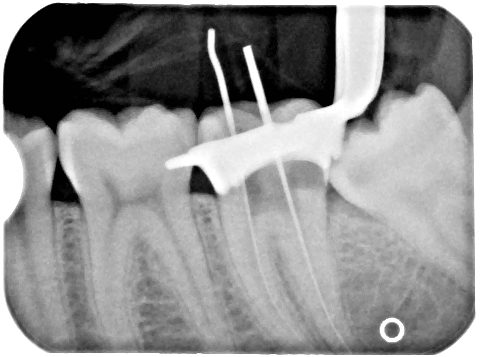

근관 치료 엑스레이 사진

• '''방사선 사진 이용법(X-ray method)'''

근관장 측정에 많이 사용되는 방법으로, 방사선 사진상에서 근관장은 해당 치아의 참조점(reference point)에서 치아 뿌리 끝보다 0.5~1mm 상방에 도달한 근단공의 가장 좁은 부위까지의 거리를 잰 값이 된다. 임상에서는 방사선 사진에서 측정한 치아의 길이에서 약 1mm를 뺀 길이를 작업장으로 산정하여 근관 치료를 시행한다.[134]